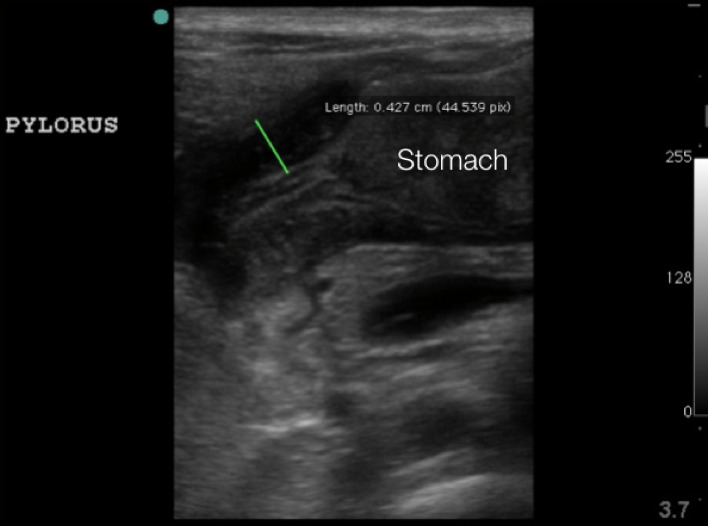

- Figure 6. Hypertrophied pyloric muscle in long axis measuring 4.3mm